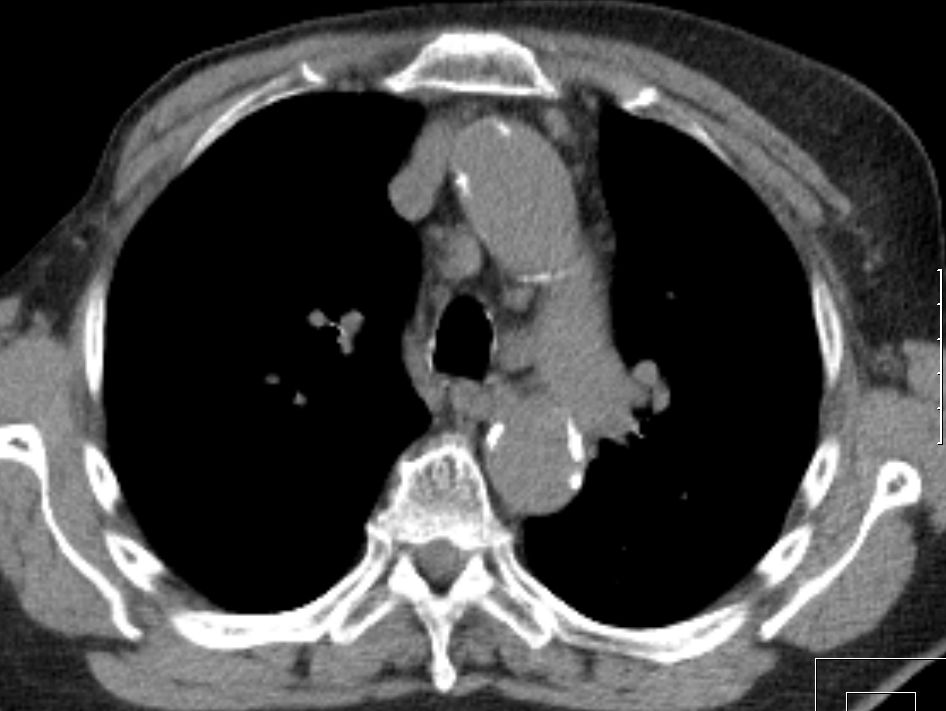

75-jährige Frau mit triple-negativem

Mammakarzinom. Chemotherapie abgelehnt. Im Planungs-CT

Lymphknotenvergrößerung mediastinal und parasernal.![]() | ||